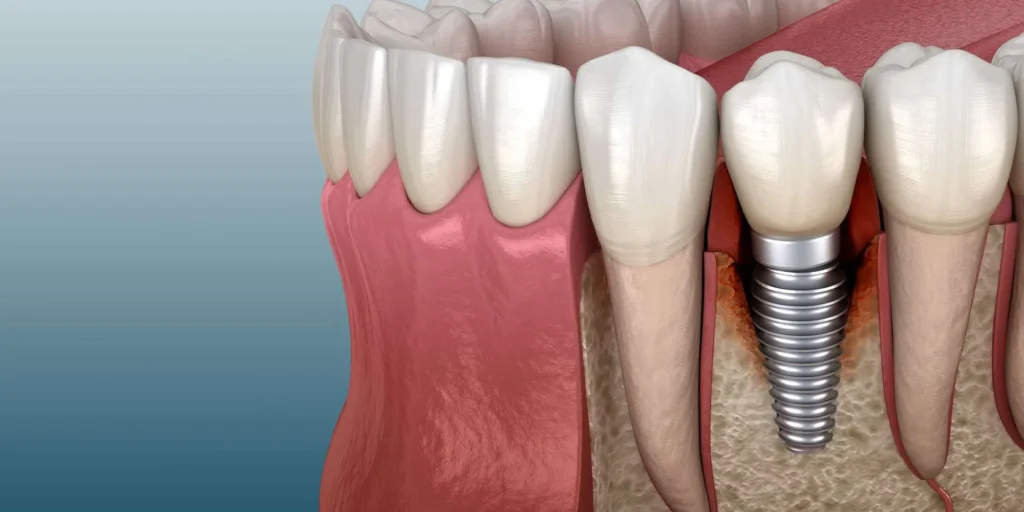

Dental implants may sometimes fail due to reasons like gum infection around the implant (peri-implantitis), incomplete bone integration, or improper chewing forces. Other factors contributing to dental implant failure include smoking, uncontrolled diabetes, or insufficient dental expertise. Warning signs, such as implant looseness, persistent pain, swelling, or bleeding around the implant, require immediate dental attention.

Dental implants can fail for several key reasons. The most common cause is gum infection around the implant (peri-implantitis), which occurs due to bacterial buildup and poor oral hygiene. Other factors leading to dental implant failure include failed bone integration, improper chewing forces, and medical conditions like uncontrolled diabetes or osteoporosis. Technical errors during surgery, such as incorrect implant placement or damage to surrounding tissues, may also cause treatment failure.

Loose Implant

When an implant moves during clinical examination, it’s one of the clearest signs of treatment problems. This typically occurs due to failed bone integration (osseointegration failure) or progressive bone loss around the implant. Dentists assess mobility using specialized tools like periodontal probes or controlled pressure tests. A loose implant often accompanies other symptoms like pain, gum inflammation, or visible position changes, which could ultimately lead to dental implant failure if unaddressed.

Bone Loss Around Implants

Progressive bone loss visible in consecutive X-rays serves as a critical warning sign for implant complications. While 0.5-1mm of annual bone loss is normal during the first year post-placement, excessive loss exceeding 2mm/year or visibly progressing in serial images indicates trouble. Radiographs typically reveal this as reduced bone density near the implant’s neck and dark spaces around it, which, if left unchecked, could ultimately lead to dental implant failure.

Peri-implantitis: A Serious Threat to Dental Implants

Peri-implantitis is a progressive inflammatory infection in the tissues surrounding an implant and one of the primary causes of implant failure, characterized by distinct symptoms that typically include gum inflammation, redness, bleeding during probing, and, in advanced cases, pus discharge from the area. A probing depth exceeding 4mm with bleeding, combined with visible bone loss on X-rays, confirms the diagnosis. If left untreated, this condition can lead to severe bone deterioration and ultimately dental implant failure, resulting in implant loss.